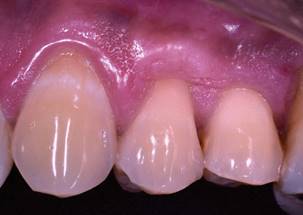

The connective tissue graft was inserted in the recipient bed, leaving 2 mm. exposed (final position); the surgical wound was washed with saline solution and dried with gauze. Finally, 2 layers of tissue adhesive (PeriAcryl®90 HV, GluStitch Inc., Vancouver, Canada) were applied on the surface of the tissues using a rubbing technique, until a compact and stable structure was achieved (3 layers of adhesive) (Fig. 2). The whole procedure took 20 minutes.